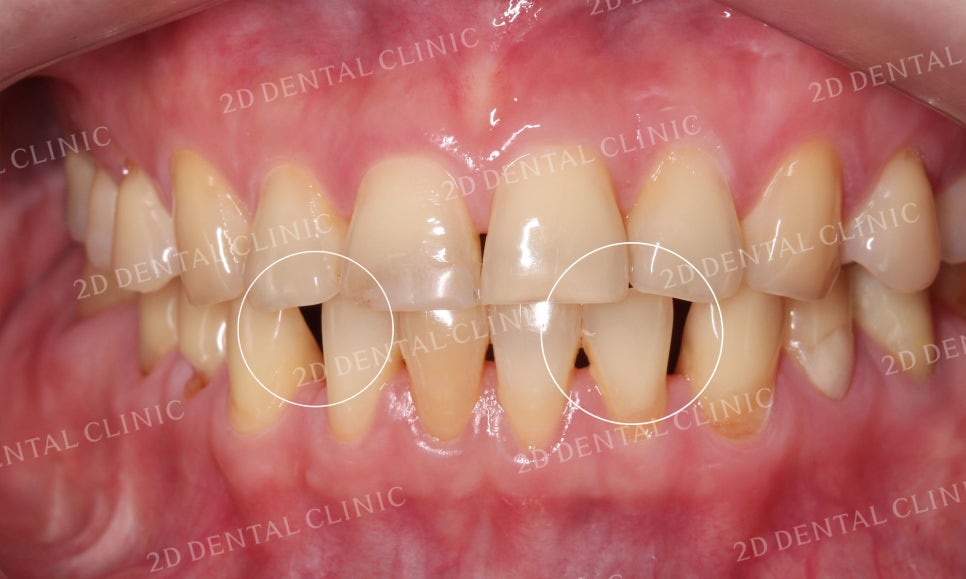

블링스 시술 전 환자분의 치아 상태는

치아가 전체적으로 누렇게 착색되어 있고

잇몸의 퇴축으로 인해 치아 뿌리들이 조금씩

드러나고 있는 상황이었습니다.

또한 치아 사이의 공간이 있어서

치간이개로 인한 블랙트라이앵글도

발견되었고요.

심미적으로도 좋지 못하고,

환자분께서도 약해진 잇몸과 치아때문에

스트레스를 받고 계셨습니다ㅠ

블링스 시술 전후 전치부의 사진입니다.

잇몸의 퇴축으로 치아 사이에 빈틈이 보이던

시술 전과 달리 시술 후 치아가 예쁘게 자리잡힌 모습이네요~